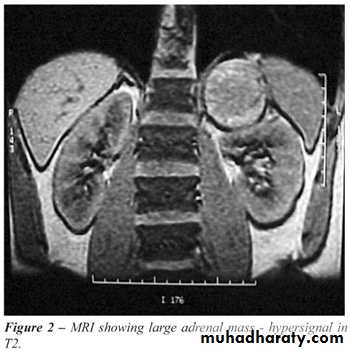

c. M.R.I for = .

. Anatomical diagnosis by CT scan or MRI abd.